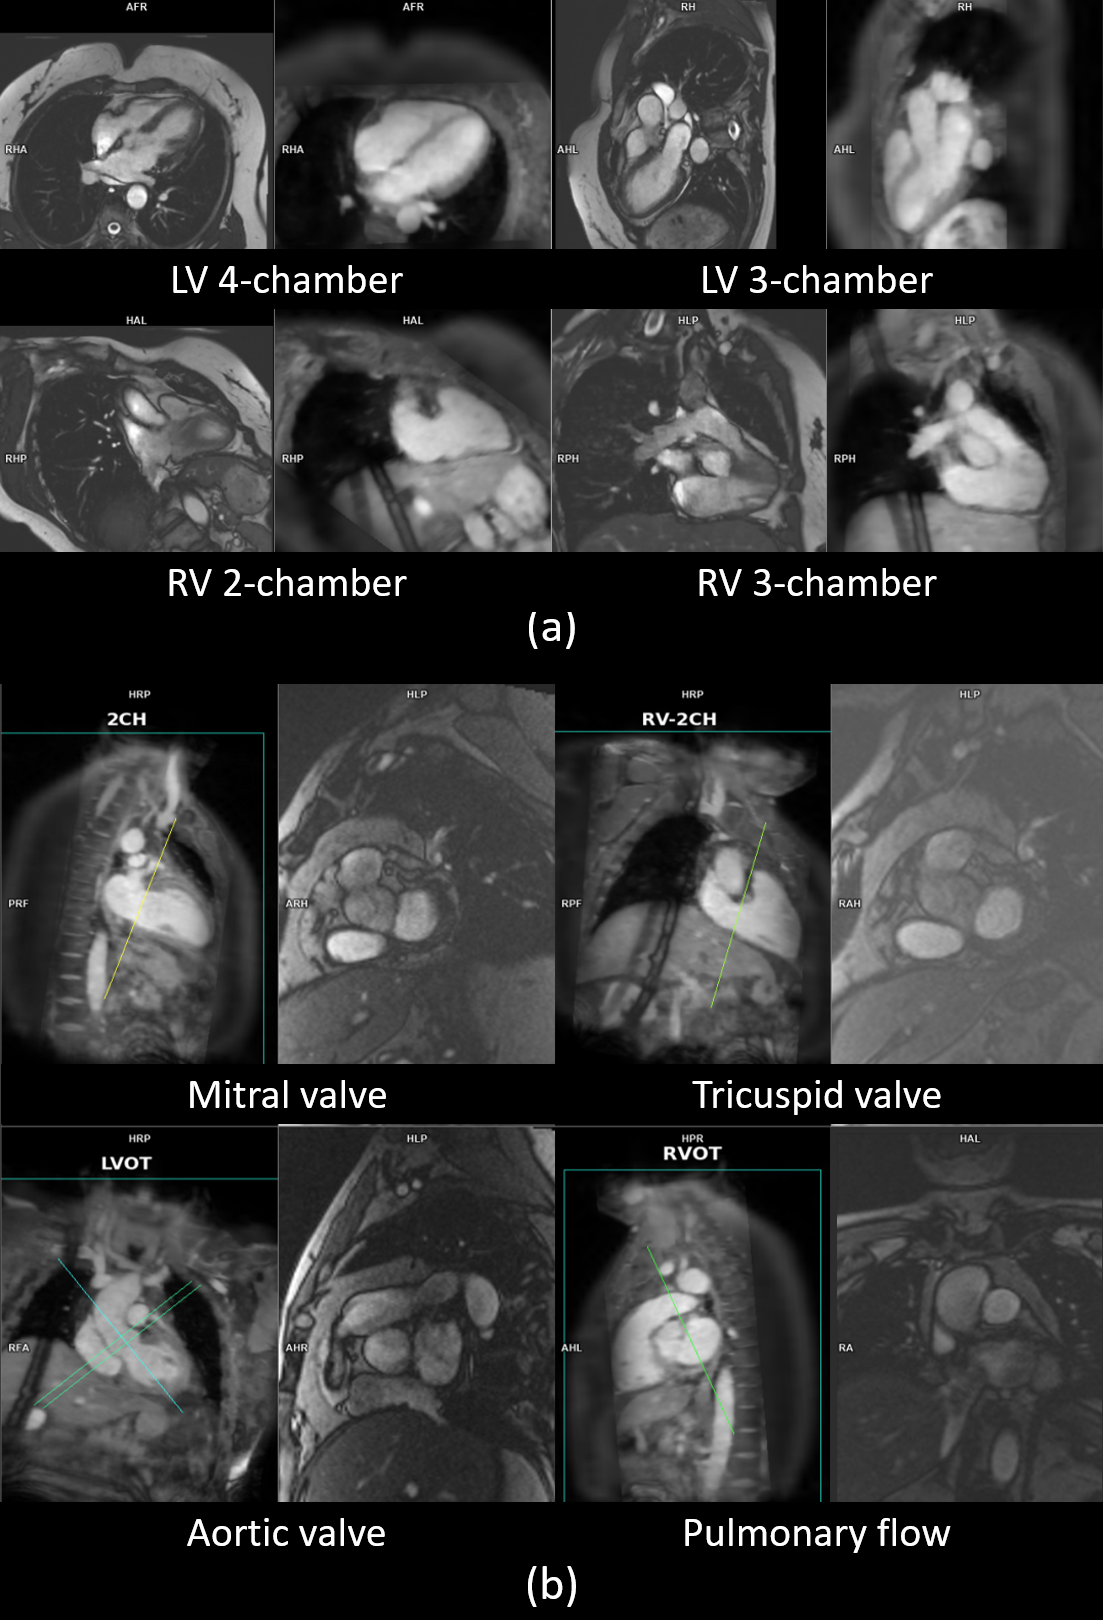

Figure 2: Examples of low scores. (a) Cases where an “Incorrect (0)” score was given for the cine, but the corresponding MPR was rated “Excellent (2)”, indicating a breath-hold mismatch rather than a misdetection of the AI algorithm. (b) Cases where an “Acceptable (1)” score was given, either due to suboptimal angulation (mitral, tricuspid, pulmonary) or too low position of the aortic valve.